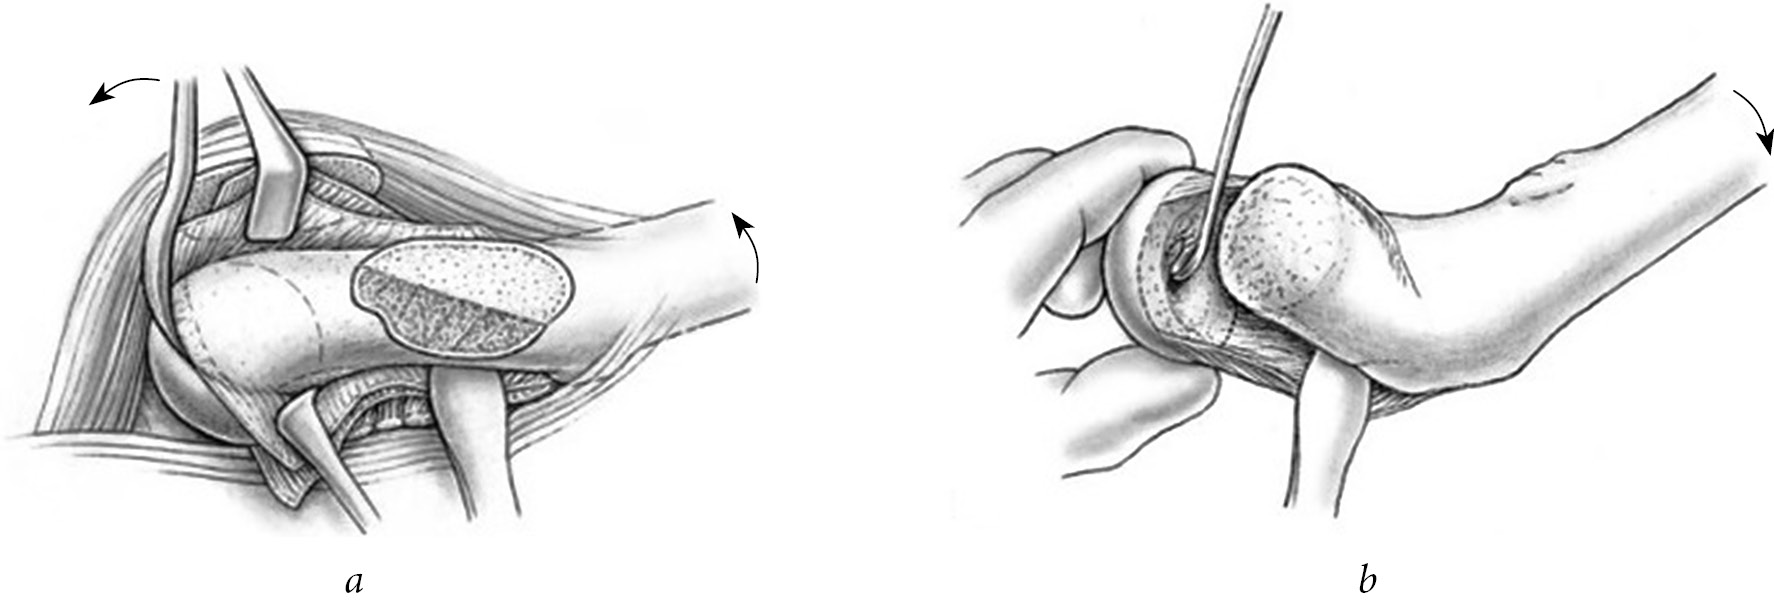

The most detailed description of the modified Dunn surgery technique, in our opinion, was given by Ziebarth et al. in 2009 [19]. In our work, we strove for strict adherence to the author’s technique, including all the described details of the intervention. Particular attention was paid to determining the direction and length of the joint capsule dissection (Z-shaped during surgery on the right and anti-Z-shaped during surgery on the left joint) (Fig. 1, a) and careful subperiosteal isolation of the femoral neck, allowing us to obtain a massive graft nourishing the epiphysis (Fig. 1, b). In addition, in order to avoid damage to the formed nourishing graft containing ascending branches of a. circumflexa femoris medialis, it is necessary to be extremely careful when performing a neck osteotomy (Fig. 2, a) and removal of the subepiphyseal trabecular bone with the remains of the growth plate (Fig. 2, b). To determine the presence and intensity of blood flow in the epiphysis, immediately after dislocation of the femoral head from the joint cavity, a hole in its anterior pole was drilled with a Kirschner wire. The absence of bleeding from the hole after osteosynthesis of the epiphysis and metaphysis indicated excessive tension of the nourishing graft; therefore, it was necessary to perform additional shortening of the neck. Depending on the severity of regional osteoporosis, two or three wires with a diameter of 2.5 mm were used to fix the epiphysis with bent threads on the end, which were brought into different planes from the side of the epiphysis (from the fovea capitis ossis femoris) and metaphysis.

Fig. 2. Technique of modified Dunn surgery: a — osteotomy of the femoral neck; b — removal of the subepiphyseal trabecular bone with the remains of the growth plate [19]